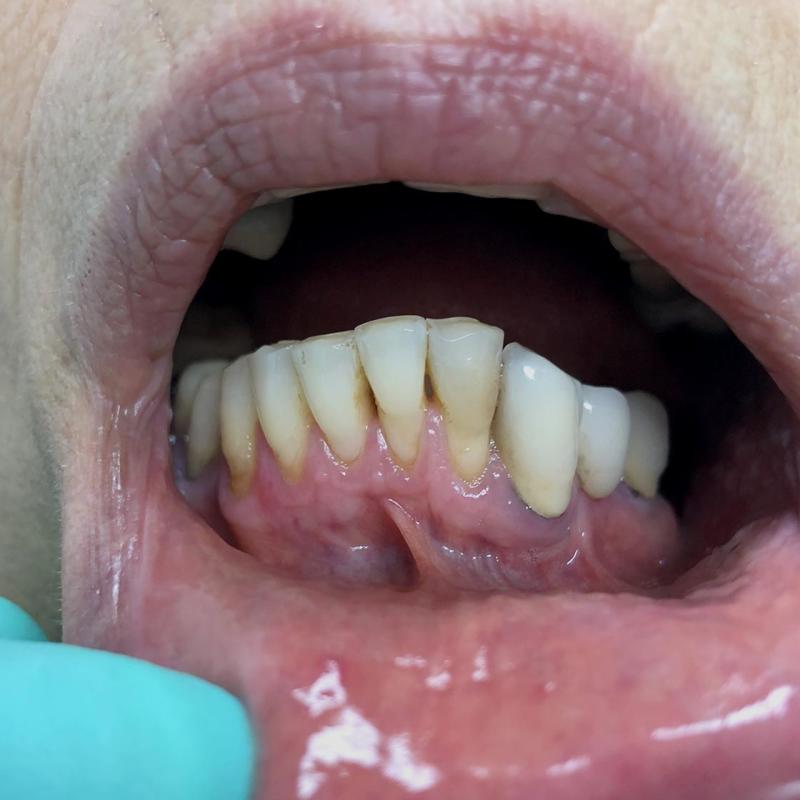

La parodontologia controlla il benessere delle strutture portanti dei denti (gengive e osso di sostegno) cercando di prevenire o curare la piorrea che nella popolazione adulta è la più frequente causa di perdita dei denti.

Oggi più che mai viene richiesta la copertura di esposizioni radicolari mediante la chirurgia estetica mucogengivale. Inoltre con la cura della piorrea si mantiene in buono stato la salute generale del paziente prevenendo complicanze cardiovascolari e diabetiche.